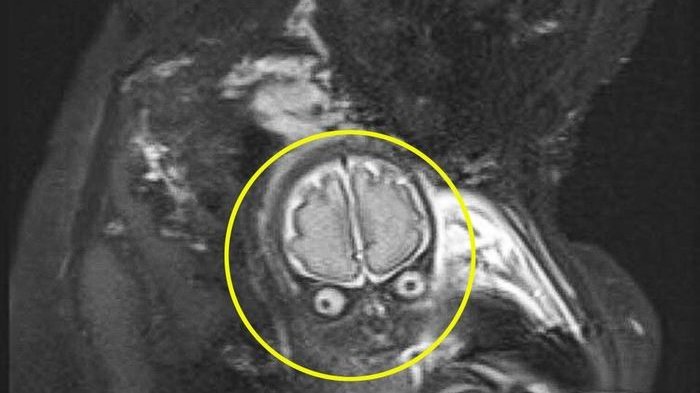

Lucas saat dilakukan pemindaian MRI di usia kandungannya 30 minggu.

Hasil pemindaian MRI menunjukkan wajah si kecil Lucas, tampak marah dan melotot ke kamera dengan matanya yang besar dan garis luar otaknya terlihat jelas.

Itu tampak sangat mirip dengan karakter alien dalam film yang dirilis tahun 1996.

Foto tersebut juga memberikan gambaran yang dibutuhkan pasangan ini ketika dokter yang menangani menemukan cairan berlebih di otak Lucas.

Pemindaian MRI ini dilakukan pada Februari 2017.